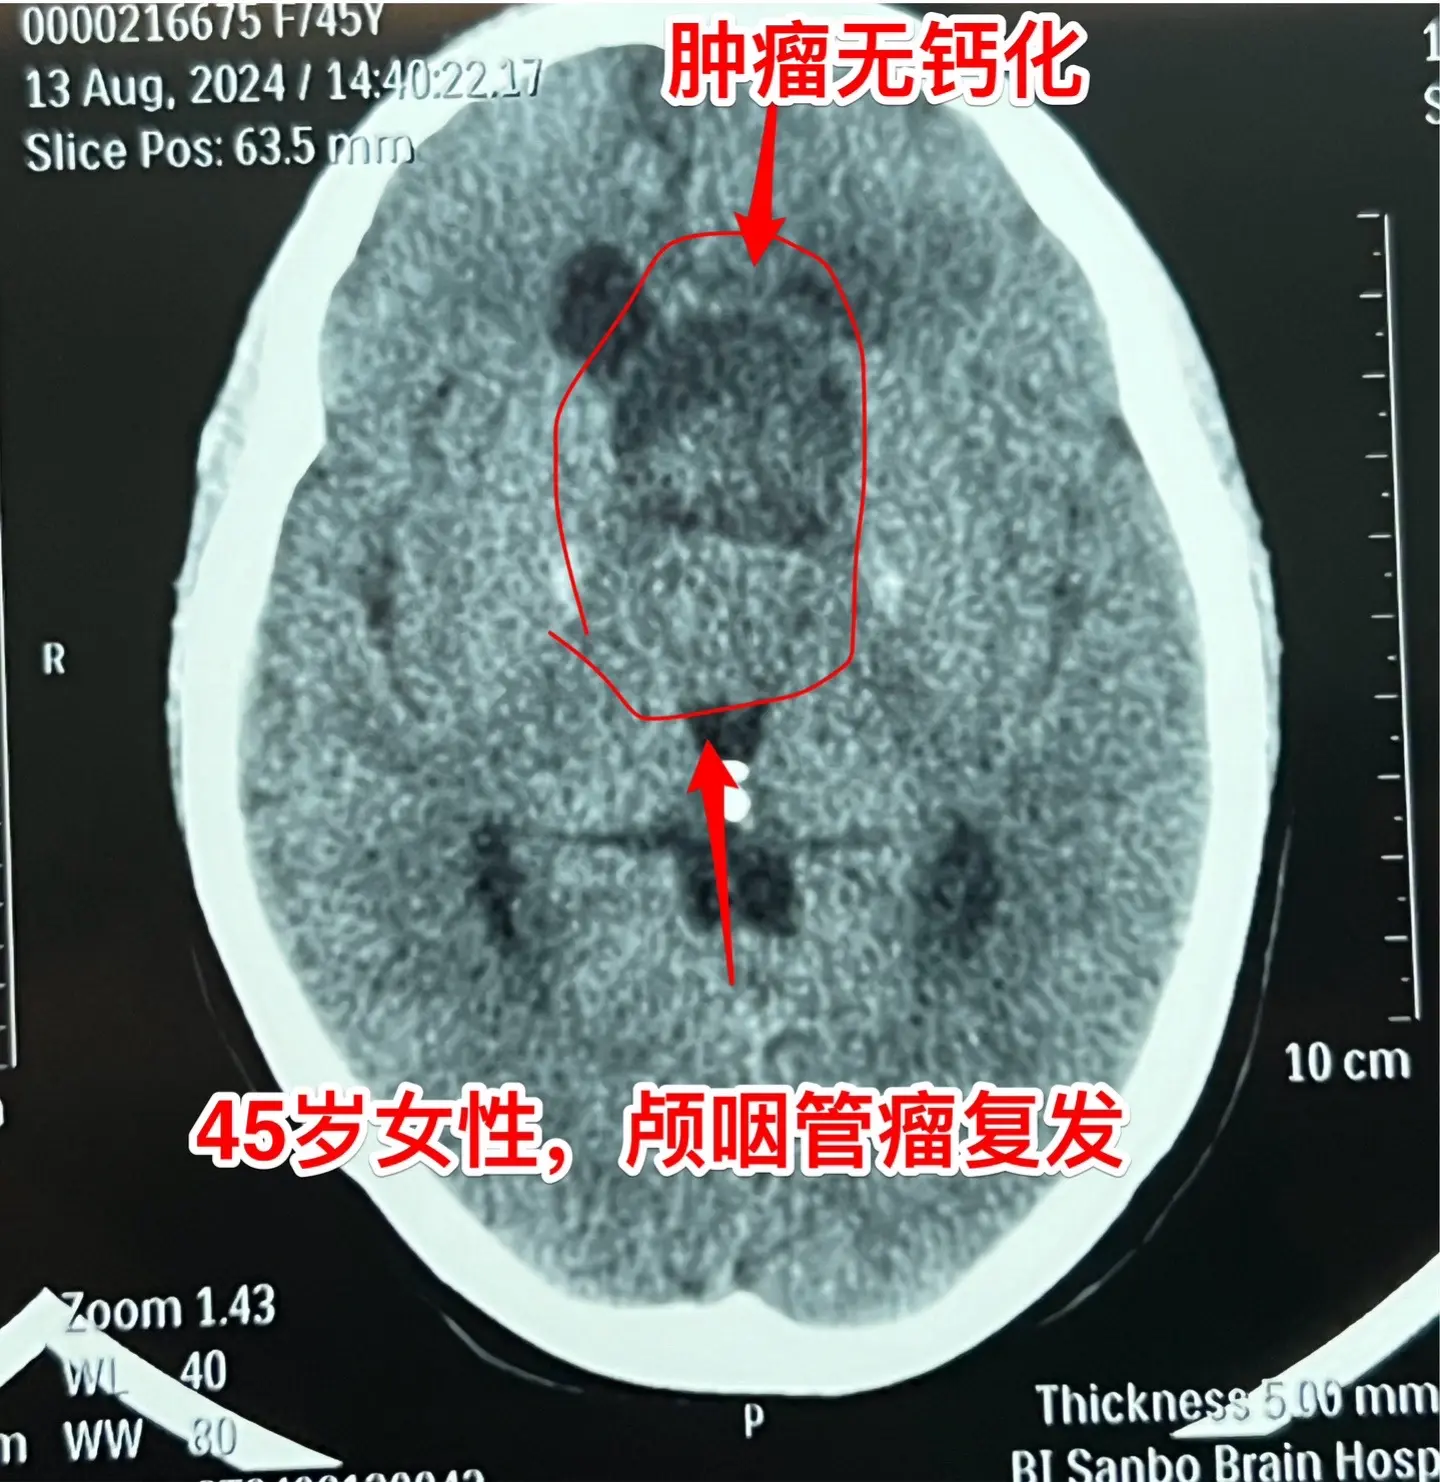

巨大的颅咽管瘤。45岁浙江女性,在外院作了颅咽管瘤手术不到一年,作磁共振显示肿瘤复发,而且体积巨大。 病人视力很差,记忆力也差,精神不好。 这么大的颅咽管瘤一般是需要作手术的。显而易见是这样的手术是很有难度的,很考验医生的技术和能力! 从影像学资料可以看出,这是乳头型颅咽管瘤。如果害怕作手术,对于运气好、经济状况好的病人,也可以试一试靶向药,也许有效。 这个病人选择了作手术!8月16日我们经过九个小时的紧张奋战,将肿瘤完全切除了。手术后CT结果很好。